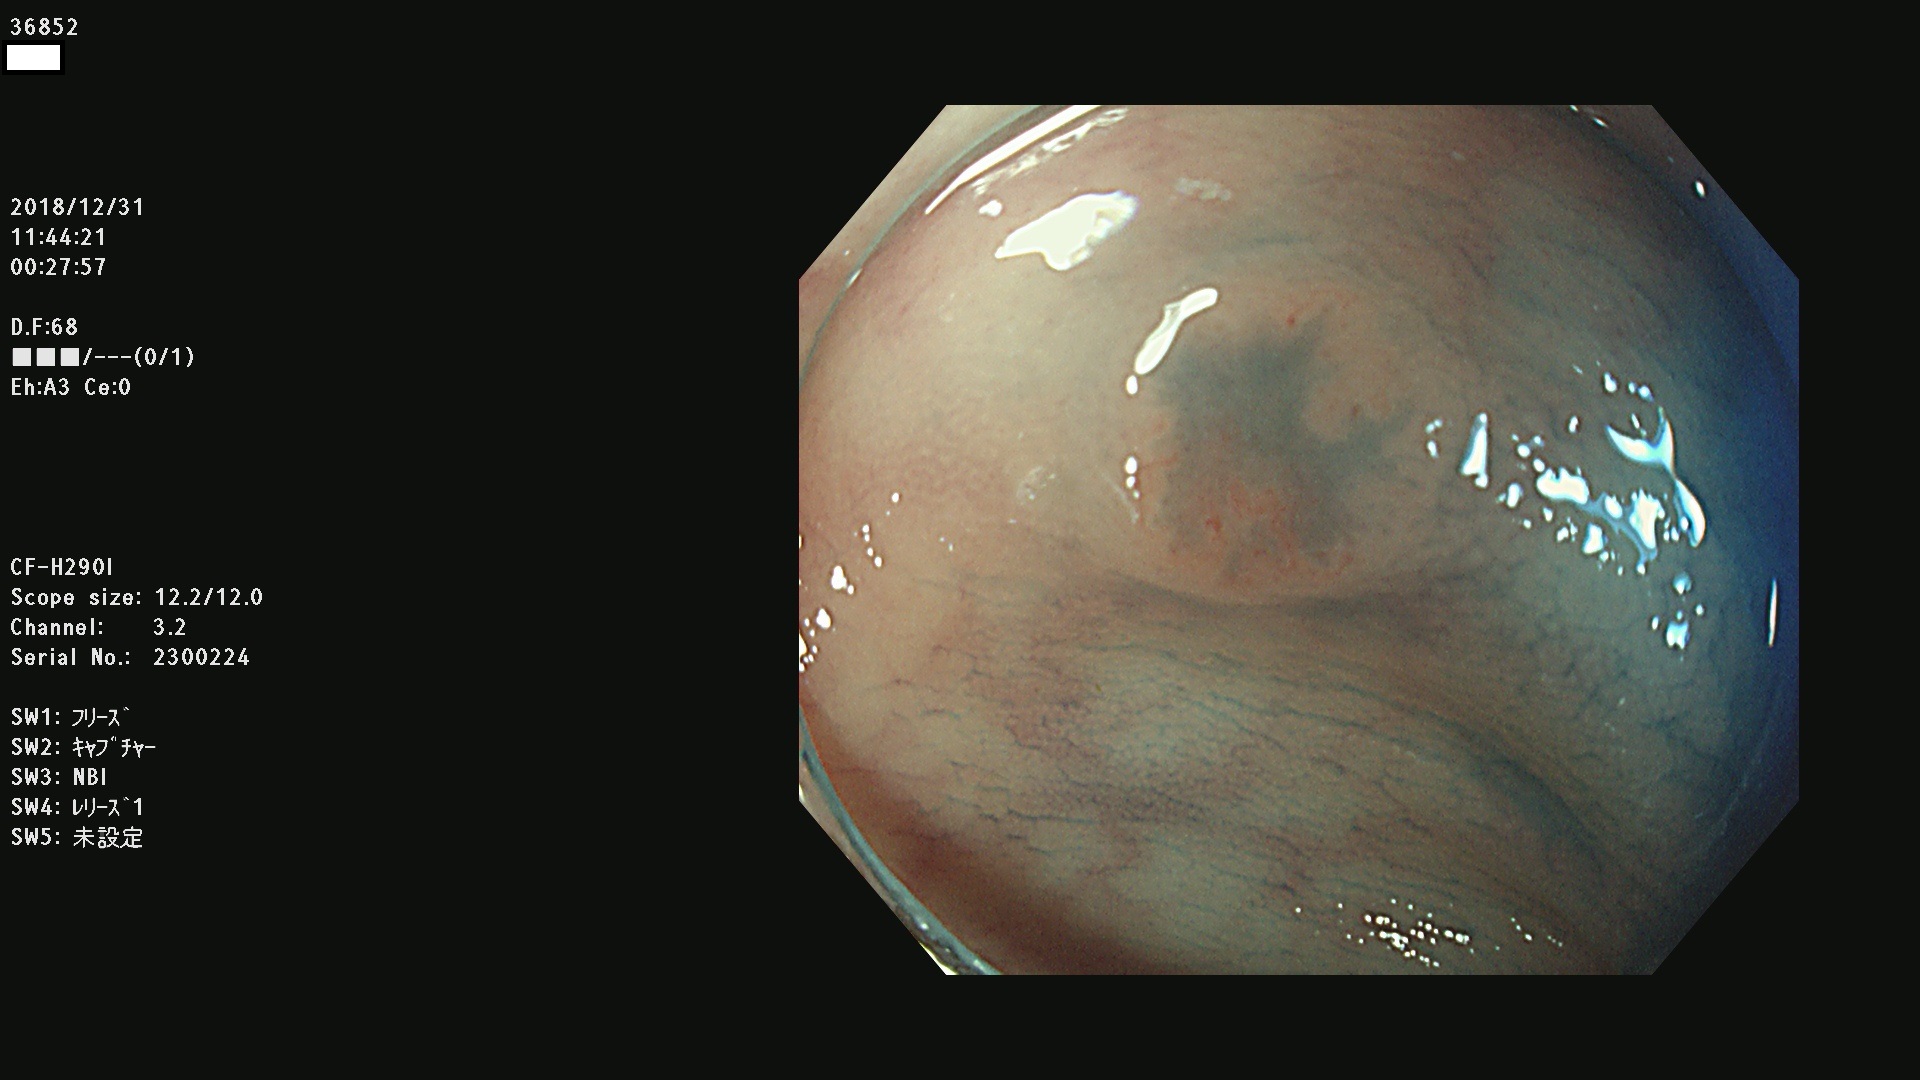

36804 36806 36807 36808 36809 36810 36811 36813 36815 36816 36817 36818 36820 36821 36822 36824 36825 36826 36828 36829 36830 36831 36832 36833 36834 36835 36837 36840 36841 36842 36845 36846 36848 36849 36851 36852 36853 36854 36855 36857 36859 36860 36861 36862(SSAPのみ) 36863 36864 36866 36868 36869 36870 36873 36875 36877 36878 36879 36881 36882 36883 36884 36885 36886 36887 36888 36889 36891 36892 36893 36894 36895 36896 36897 36898 36899

発見困難で危険性の高い平坦型病変(上記100名より抽出)